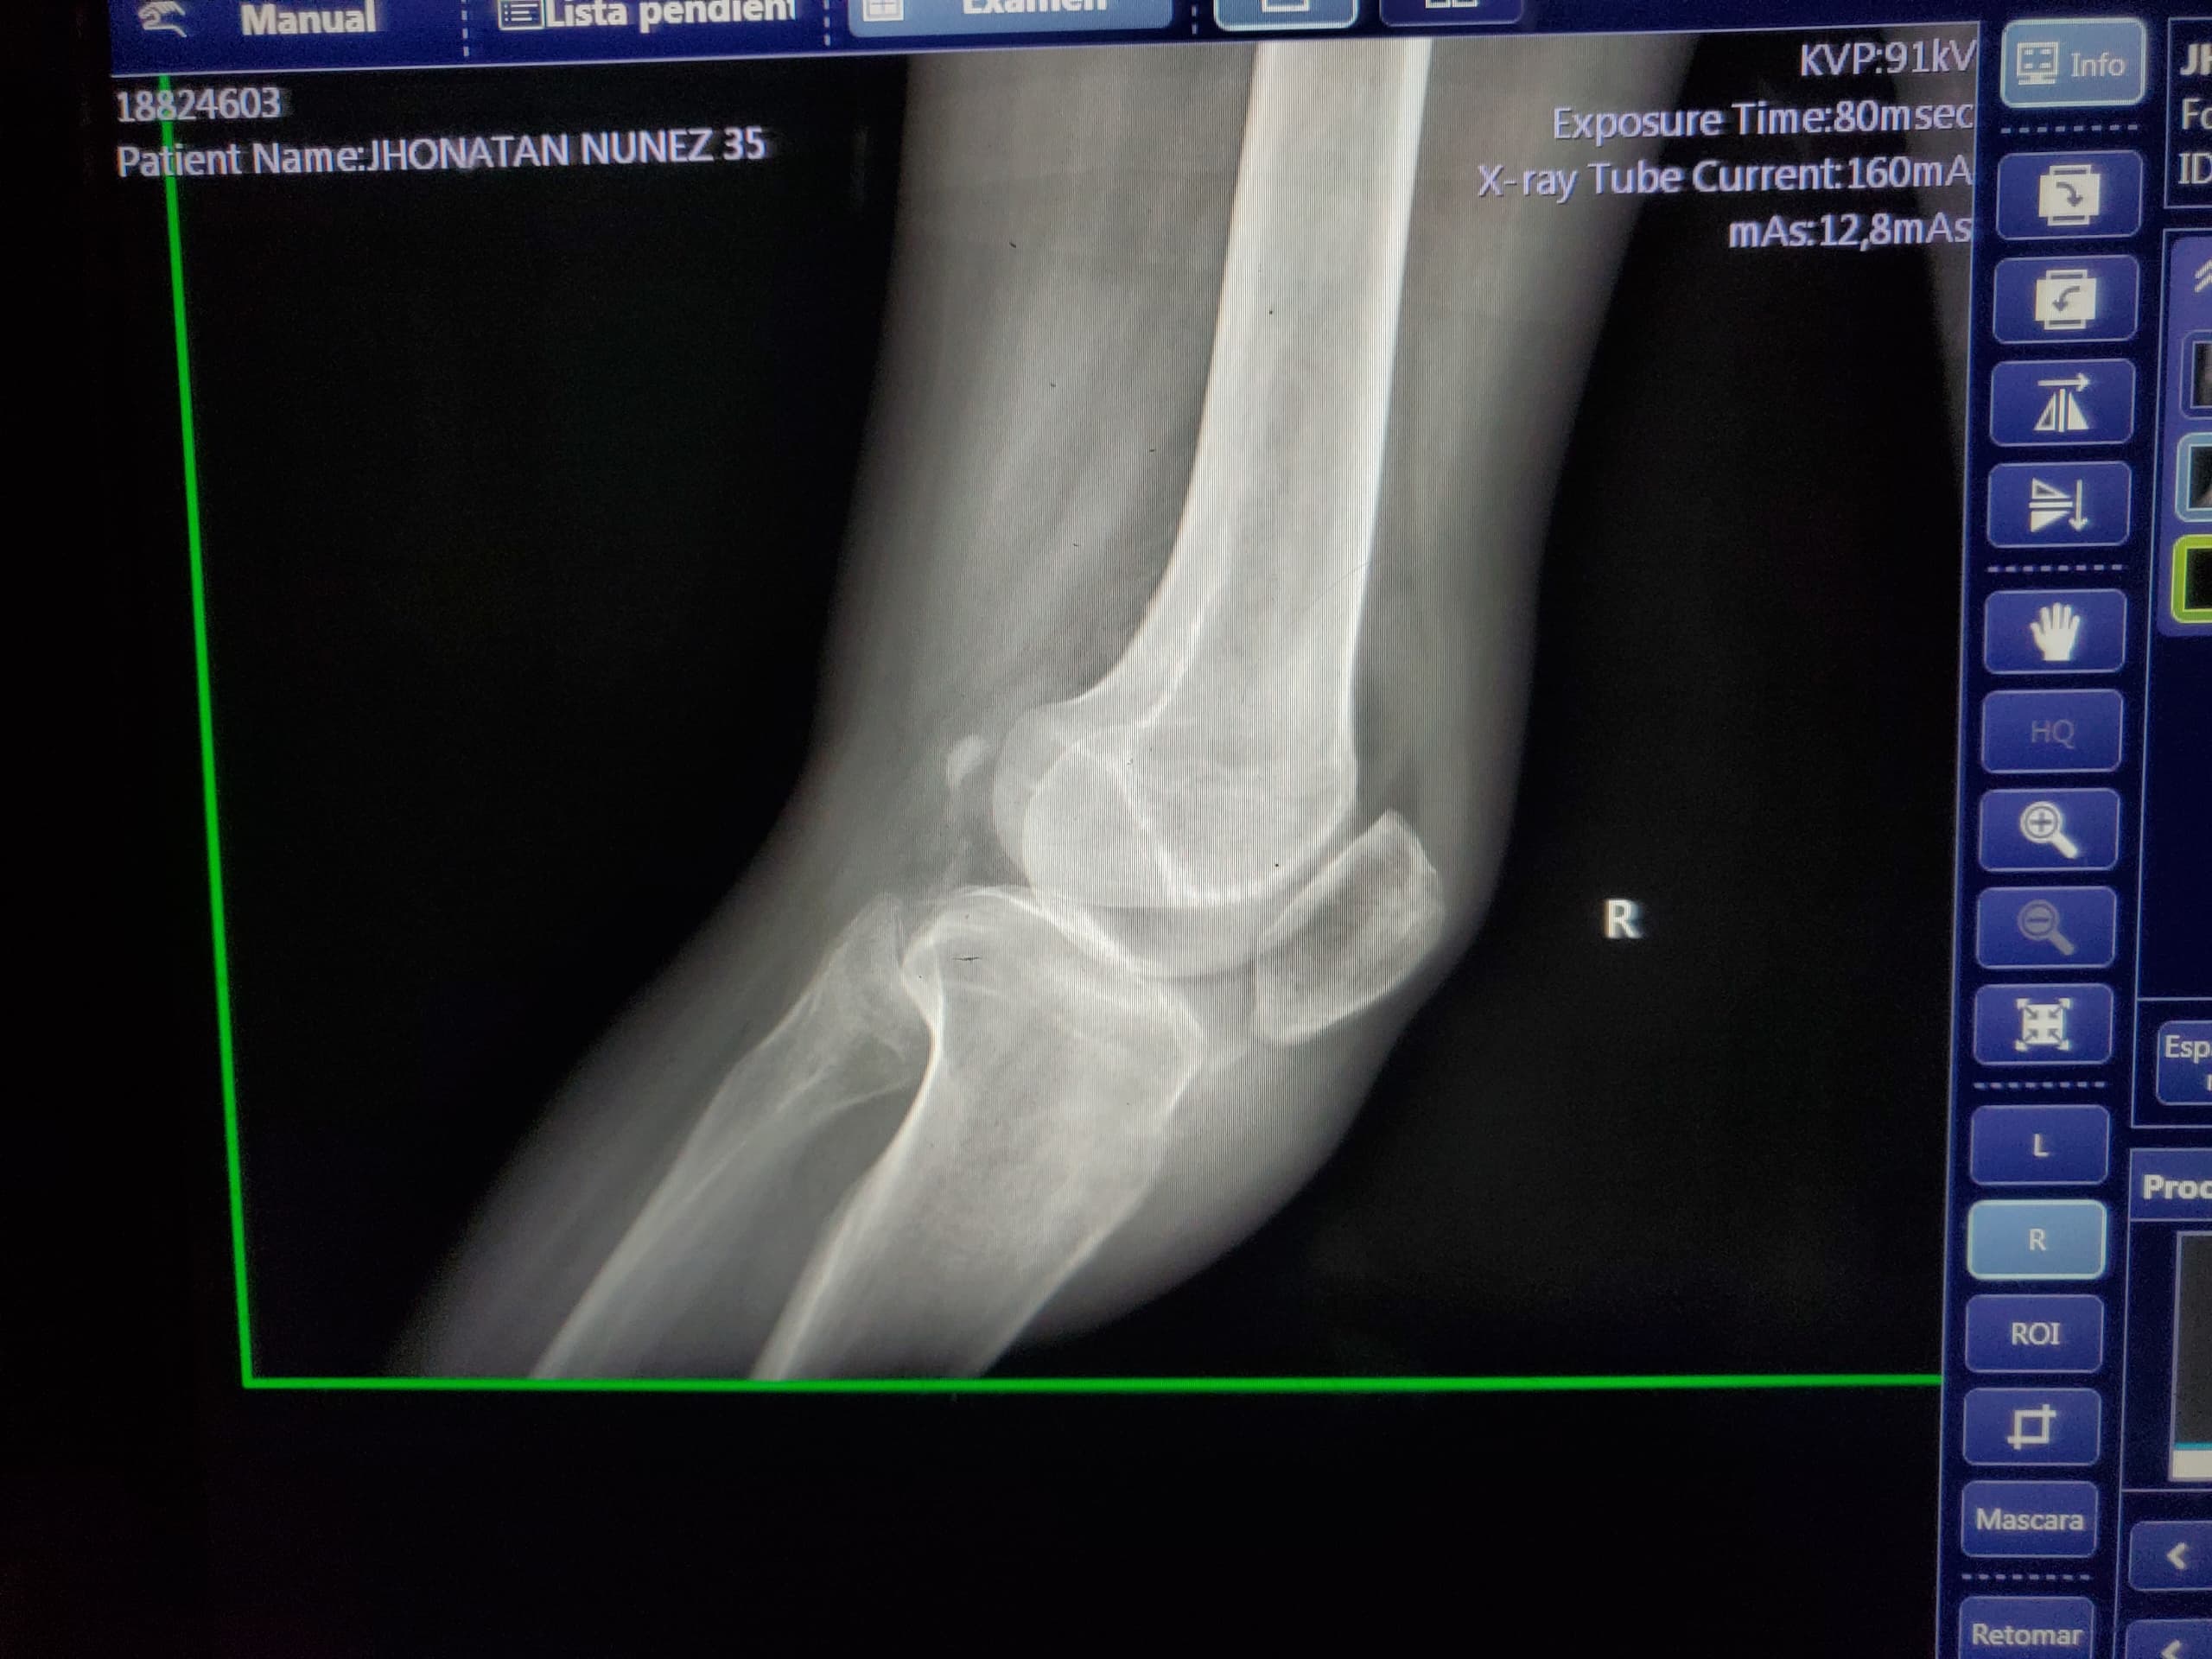

El periodista marabino Jonathan Núñez, de 35 años, requiere con urgencia una resonancia magnética de rodilla izquierda simple por un derrame articular en su rodilla izquierda debido a una fuerte caída suscitada el pasado jueves 24 de octubre.

Tras el impacto, al comunicador social le realizaron un procedimiento médico denominado artrosentesis o retiro del líquido de la zona afectada.

“Debido a la distrofia que padezco he tenido varias caídas, pero las más fuertes han sido en 2019, por la que me tuvieron que extraer 20 centímetros cúbicos (cc) de líquido de la rodilla izquierda, y ahora esta que me pasó el 24 de octubre, por la que me sacaron 40 cc de líquido del mismo lugar, por lo que necesito con urgencia la resonancia magnética y ayuda para gastos médicos, que son muy elevados”, señaló.

El periodista amerita la resonancia para que los especialistas determinen el por qué después de 20 días de la caída no puede apoyar con normalidad la articulación afectada.